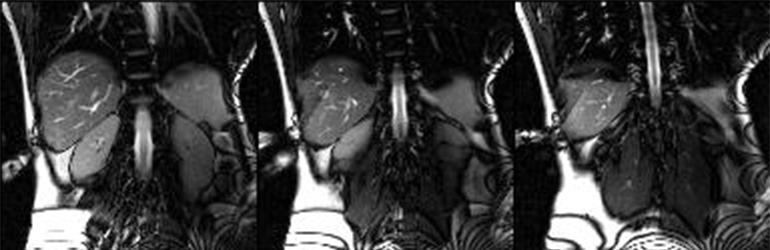

An abscess is a localized collection of pus caused by infection, which can occur in the abdomen, organs, or soft tissue and lead to pain, fever, and general deterioration. Percutaneous abscess drainage is a minimally invasive treatment in which a thin catheter is inserted into the abscess under imaging guidance (ultrasound, CT, or MRI). This allows continuous drainage of pus, relieving pressure and promoting healing. The technique enables precise catheter placement while minimizing damage to surrounding tissue and often avoids major surgery. It is typically combined with antibiotic therapy. In our group, abscess drainages are routinely performed using modern image guidance, helping patients recover faster and reducing hospital stays.